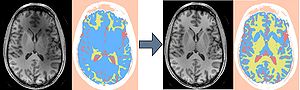

Publication: PLoS One. 2015 Dec 3;10(12):e0143821. PMID: 26633302 | PDF Authors: Gutierrez S, Descamps B, Vanhove C. Institution: Medical Image and Signal Processing Group, Ghent University-iMinds Medical IT department, Ghent, Belgium. Background/Purpose: Computed tomography (CT) is the standard imaging modality in radiation therapy treatment planning (RTP). However, magnetic resonance (MR) imaging provides superior soft tissue contrast, increasing the precision of target volume selection. We present MR-only based RTP for a rat brain on a small animal radiation research platform (SARRP) using probabilistic voxel classification with multiple MR sequences. Six rat heads were imaged, each with one CT and five MR sequences. The MR sequences were: T1-weighted, T2-weighted, zero-echo time (ZTE), and two ultra-short echo time sequences with 20 μs (UTE1) and 2 ms (UTE2) echo times. CT data were manually segmented into air, soft tissue, and bone to obtain the RTP reference. Bias field corrected MR images were automatically segmented into the same tissue classes using a fuzzy c-means segmentation algorithm with multiple images as input. Similarities between segmented CT and automatic segmented MR (ASMR) images were evaluated using Dice coefficient. Three ASMR images with high similarity index were used for further RTP. Three beam arrangements were investigated. Dose distributions were compared by analysing dose volume histograms. The highest Dice coefficients were obtained for the ZTE-UTE2 combination and for the T1-UTE1-T2 combination when ZTE was unavailable. Both combinations, along with UTE1-UTE2, often used to generate ASMR images, were used for further RTP. Using 1 beam, MR based RTP underestimated the dose to be delivered to the target (range: 1.4%-7.6%). When more complex beam configurations were used, the calculated dose using the ZTE-UTE2 combination was the most accurate, with 0.7% deviation from CT, compared to 0.8% for T1-UTE1-T2 and 1.7% for UTE1-UTE2. The presented MR-only based workflow for RTP on a SARRP enables both accurate organ delineation and dose calculations using multiple MR sequences. This method can be useful in longitudinal studies where CT's cumulative radiation dose might contribute to the total dose. |

Illustration of a CB-CT and five MR images of the same animal. a) Coronal CB-CT image and (b)-(f) biased field corrected and masked coronal MR images using a T1-weighted (b), T2-weighted (c), ZTE (d), UTE1 (e) and UTE2 (f) sequence. All CB-CT images were first co-registered using 3D Slicer version 3.6.3 by rigid body transformations using normalized mutual information. |